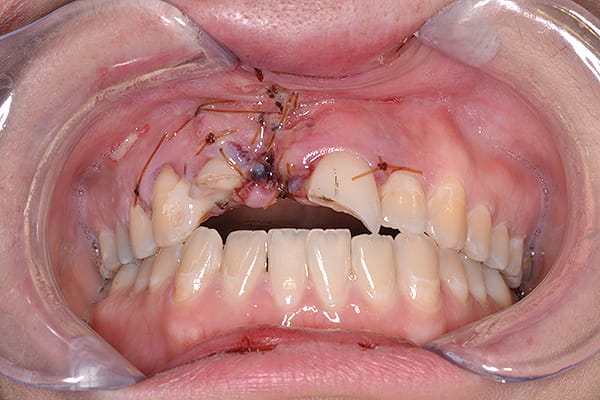

Figure 9

Figure 9 Esthetic re-evaluation with an ideal fixed temporary provisional. Significant soft tissue defects were noticed. (Fig 8 and Fig 9 courtesy of William Heggerick, DDS, prosthodontist, and Yuki Momma, RDT, Weston, Massachusetts)